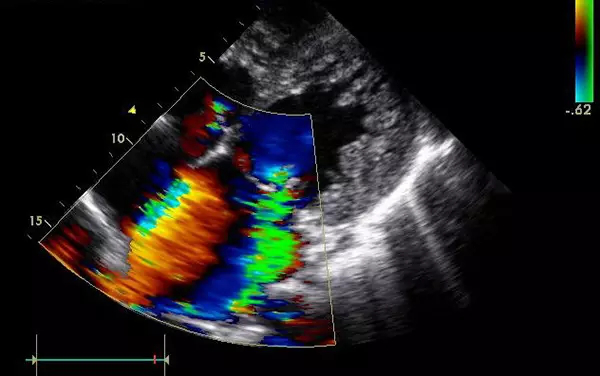

B超

B超的原理是用超聲波穿透人體,當(dāng)聲波遇到人體組織時(shí)會(huì)產(chǎn)生反射波,通過(guò)計(jì)算反射波成像。

優(yōu)點(diǎn):多方向觀察,實(shí)時(shí)成像。

缺點(diǎn):超聲受氣體干擾很大,對(duì)于腸道等含氣較多的器官,超聲診斷準(zhǔn)確率會(huì)降低,所以一般腸道檢查使用腸鏡。

4、腹部盆腔——除腸道外,一般超聲都能查

眾所周知的應(yīng)該就是懷孕期間胎兒的相關(guān)檢查,用B超都能看的很清楚;另外,甲狀腺等淺表器官,以及肝臟、脾臟、胰腺、腎臟、盆腔等實(shí)質(zhì)臟器,B超診斷準(zhǔn)確率都較高。

5、心臟——排除冠心病用CT,看心功能用超聲